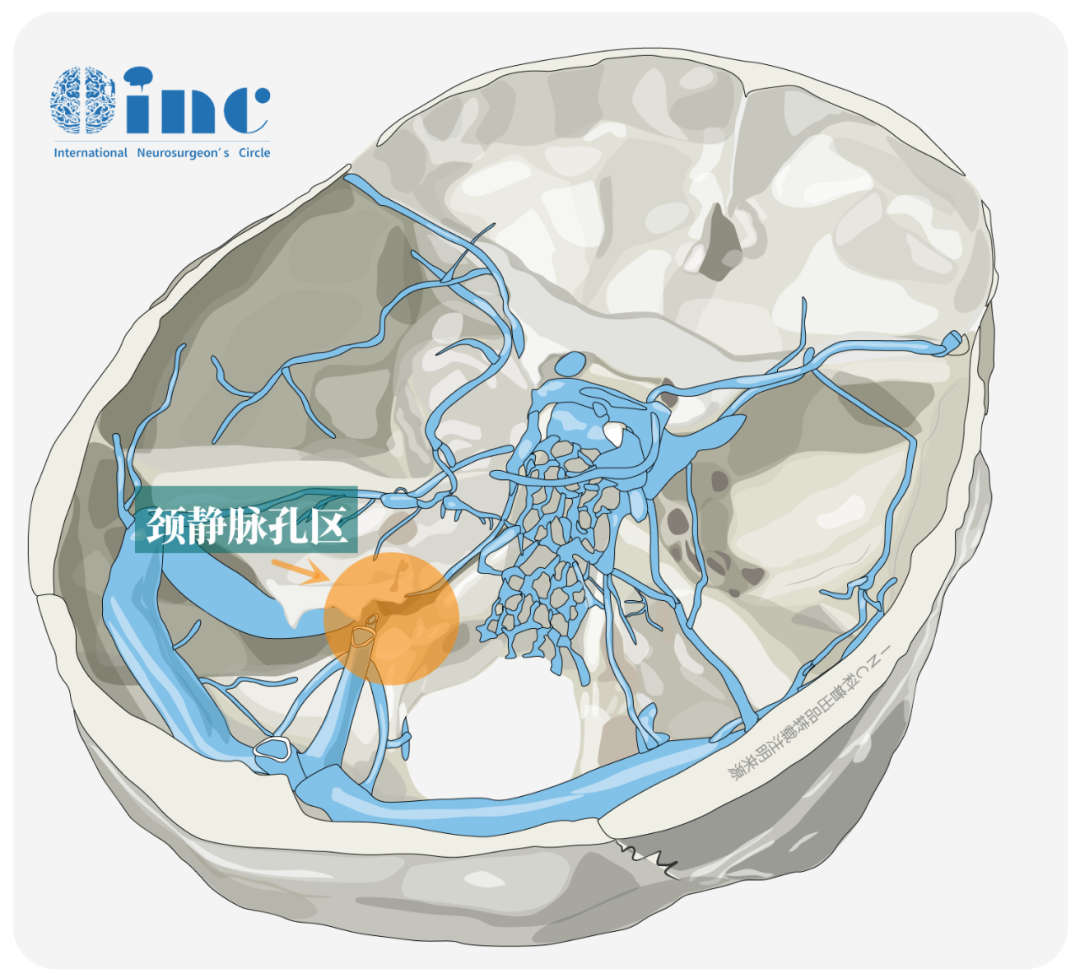

声音嘶哑、呛咳、吞咽困难……在大脑颅底位置,有这样一个地方,它是神经外科颅底手术的巨大难题之一。颈静脉孔区,手术也难以到达。此孔道很难暴露是因为其位置深在且周围毗邻诸多结构,而且其大小和形态在不同颅骨的差异、在同一颅骨上两侧的不同、同一孔道颅内端与颅外端的不同,以及其形状不规则、行程曲折、由两块颅骨构成、有诸多的颅神经和静脉管腔穿行其间。

颈静脉孔主要通行三支重要的神经——司咽喉感觉与运动的舌咽神经(CN IX)、主管发声、心跳及内脏的迷走神经(CN X),以及控制耸肩、转头的副神经(CN XI),同时颅内血液也经由颈静脉球在此处汇入颈内静脉。因此,该区域若发生肿瘤,极易压迫这些紧密相邻的神经血管,从而引发声音嘶哑、饮水呛咳、吞咽困难和搏动性耳鸣等一系列复杂症状。